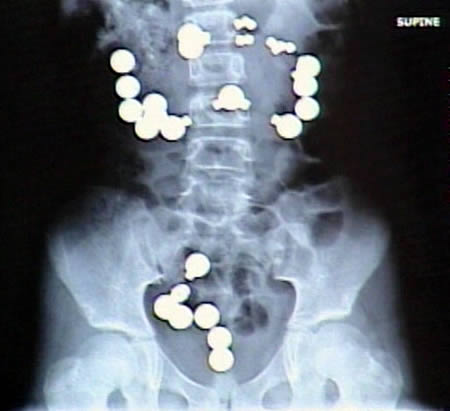

瓶は変態系統のお遊びの結果だろうな

お尻は日本でもたまーに救急に来るで

肛門 異物

でググると…

肛門に異物はよくあるらしい。やり過ぎると地主になってしまうので程ほどにね。

直腸内で破砕せざるを得なかった巨大直腸異物の1例

↑こんな感じで学会で報告されるそうだな…

そのままググれば文章出てくるわ

尻に異物が入る時はだいたい「転んだ拍子に」って言うけど医療関係者はそんな与太話は誰も信じてないだろうね。

ビーズも追加で